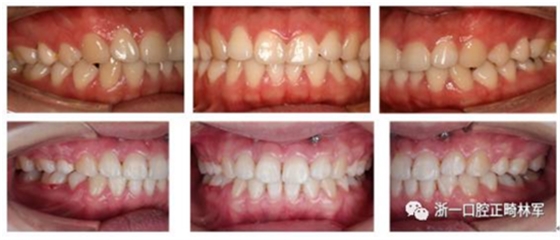

我們給她拔了4顆牙第一前磨牙,打了骨釘,來排齊牙齒,內(nèi)收前牙,改善側(cè)貌,后期又做了牙齦小手術(shù),幫她把露齦笑也解決了,最后治療結(jié)束時(shí)她不僅牙齒整齊、咬合良好,而且側(cè)貌漂亮,治療前嘴巴前突、下巴后縮、露齦笑的問題都改善了,她對此很滿意。一起來看看效果吧!

治療前后面像、口內(nèi)像對比